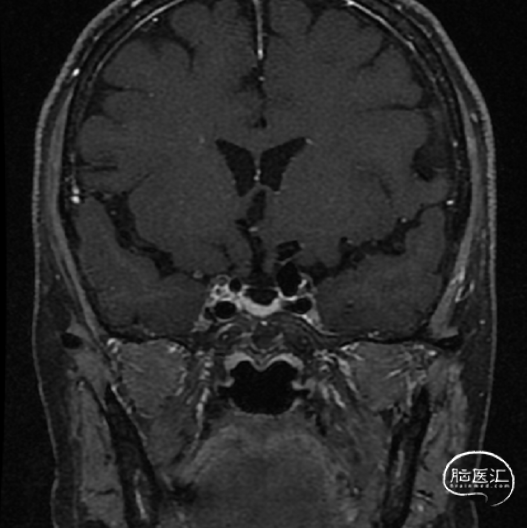

术前影像学检查结果

术前MRI

术前MRA